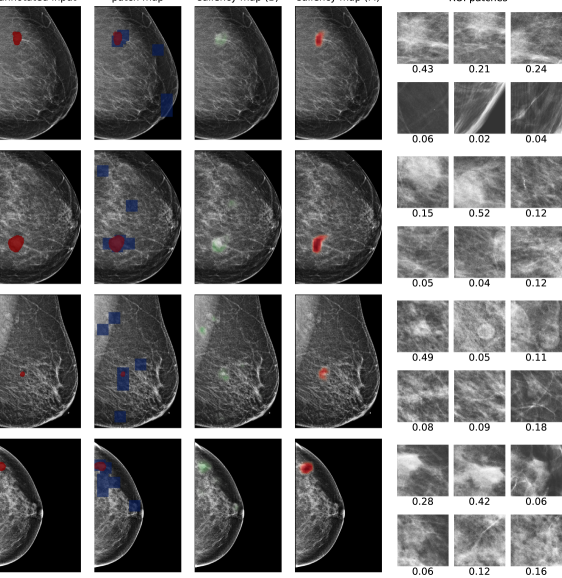

In Figure 7, we visualize saliency maps for four samples selected from the test set. In the first two examples, the saliency maps are highly activated on the annotated lesions, suggesting that our model is able to detect suspicious lesions without pixel-level supervision. Moreover, the attention is highly concentrated on ROI patches that overlap with the annotated lesions. In the third example, the saliency map for benign findings identifies three abnormalities. Although only the top abnormality was escalated for biopsy and hence annotated by radiologists, the radiologist’s report confirms that the two non-biopsied findings have a high probability of benignity and a low probability of malignancy. In the fourth example, we illustrate a case when there is some level of disagreement between our model and the annotation in the dataset. The malignancy saliency map only highlights part of a large malignant lesion with segmental coarse heterogeneous calcifications. This behavior is related to the design of : a fixed pooling threshold cannot be optimal for all sizes of ROI. The impact of is further studied in 3.6. This example also illustrates that while human experts are asked to annotate the entire lesion, CNNs tend to emphasize only the most informative regions. While no benign lesion is present, the benign saliency map still highlights regions similar to that in the malignancy saliency map, but with a lower probability than the malignancy saliency map. In fact, calcifications with this morphology and distribution can also result from benign pathophysiology [42].